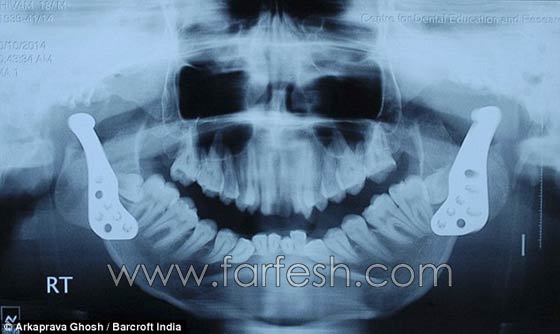

واستطاع الأطباء أخيرًا أن يعيدوا بناء الفك باستخدام مفاصل صناعية، منحت شيفام قدرات أكبرت في تحريك فمه، وأصبح بإمكانه تناول الأطعمة الصلبة، بعد أن اقتصر طعامه على مدى السنوات الماضية على السوائل، وأدى ذلك إلى تدهور حالته الصحية بشكل كبير. وأكد كل من الدكتور أجوي رويشودوري والدكتور أونجكيلا بوتيا، اللذين أجريا العملية الجراحية المعقدة في معهد العلوم الطبية الهندية، أنها المرة الأولى التي تجرى فيها هذه الجراحة.

وأوضح رئيس قسم جراحة الوجه والفكين في المعهد رويشودوري، أن الحالة التي عانى منها شيفام تدعى اندماج المفصل الفكي الصدغي، وتحدث عادة نتيجة التعرض للسقوط أو الصدمة أو عدوى جرثومية أو التهاب في الأذن.